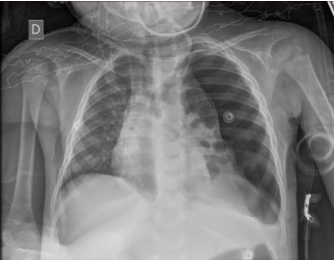

Uma paciente de dois anos de idade foi levada ao serviço de emergência com história de estar tratando uma pneumonia com cefalexina há quatro dias e, há um dia, vir apresentando piora do estado geral, prostração e inapetência. Ao exame, paciente em mau estado geral, agitada, toxemiada, afebril, com FC de 140 bpm, FR de 50 ipm, sat. de O2 de 85% em nebulização, PA de 80 x 45 mmHg, MV presente bilateralmente e diminuído à esquerda, tempo de enchimento capilar de 3 segundos e pulsos periféricos finos. Decidiu-se intubar a paciente e, durante a preparação do material e das drogas pela equipe da enfermagem, estabeleceu ventilação com bolsa-valva-máscara. Após alguns minutos, ainda antes do procedimento, a paciente iniciou crise de tosse, com FC de 180 bpm, FR de 65 ipm, sat. de O2 de 78% em ventilação com bolsa-valva-máscara e PA de 60 x 30 mmHg. A radiografia realizada na sala de emergência segue abaixo.

Com base nesse caso hipotético, assinale a alternativa que apresenta a conduta mais indicada no momento.